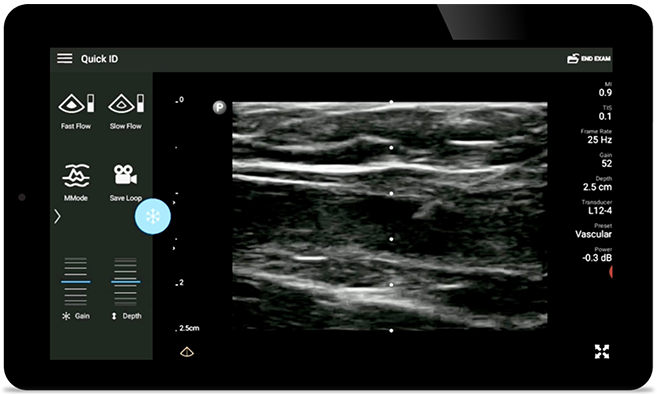

Reduceţi șansele de apariție a complicațiilor apărute în urma inserţiilor CVC

Ghidarea cu ultrasunete în timp real poate îmbunătăţi precizia şi siguranţa inserţiilor CVC.

• Interval extins al frecvenței de operare, cuprins între 4 şi 12 MHz • Dimensiunea deschiderii: 34 mm • Imagistică 2D, Doppler cu culoare reglabilă, mod M, XRES avansată şi armonică multivariată, SonoCT • Imagini de înaltă rezoluţie pentru aplicaţii superficiale: ţesut moale, vascular, superficial, musculo-scheletic şi pulmonare • Marcaj al liniei centrale • Traductor USB-C cu cablu înlocuibil